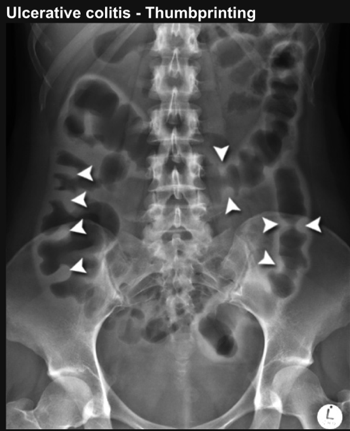

what is seen on AXR

thumb printing